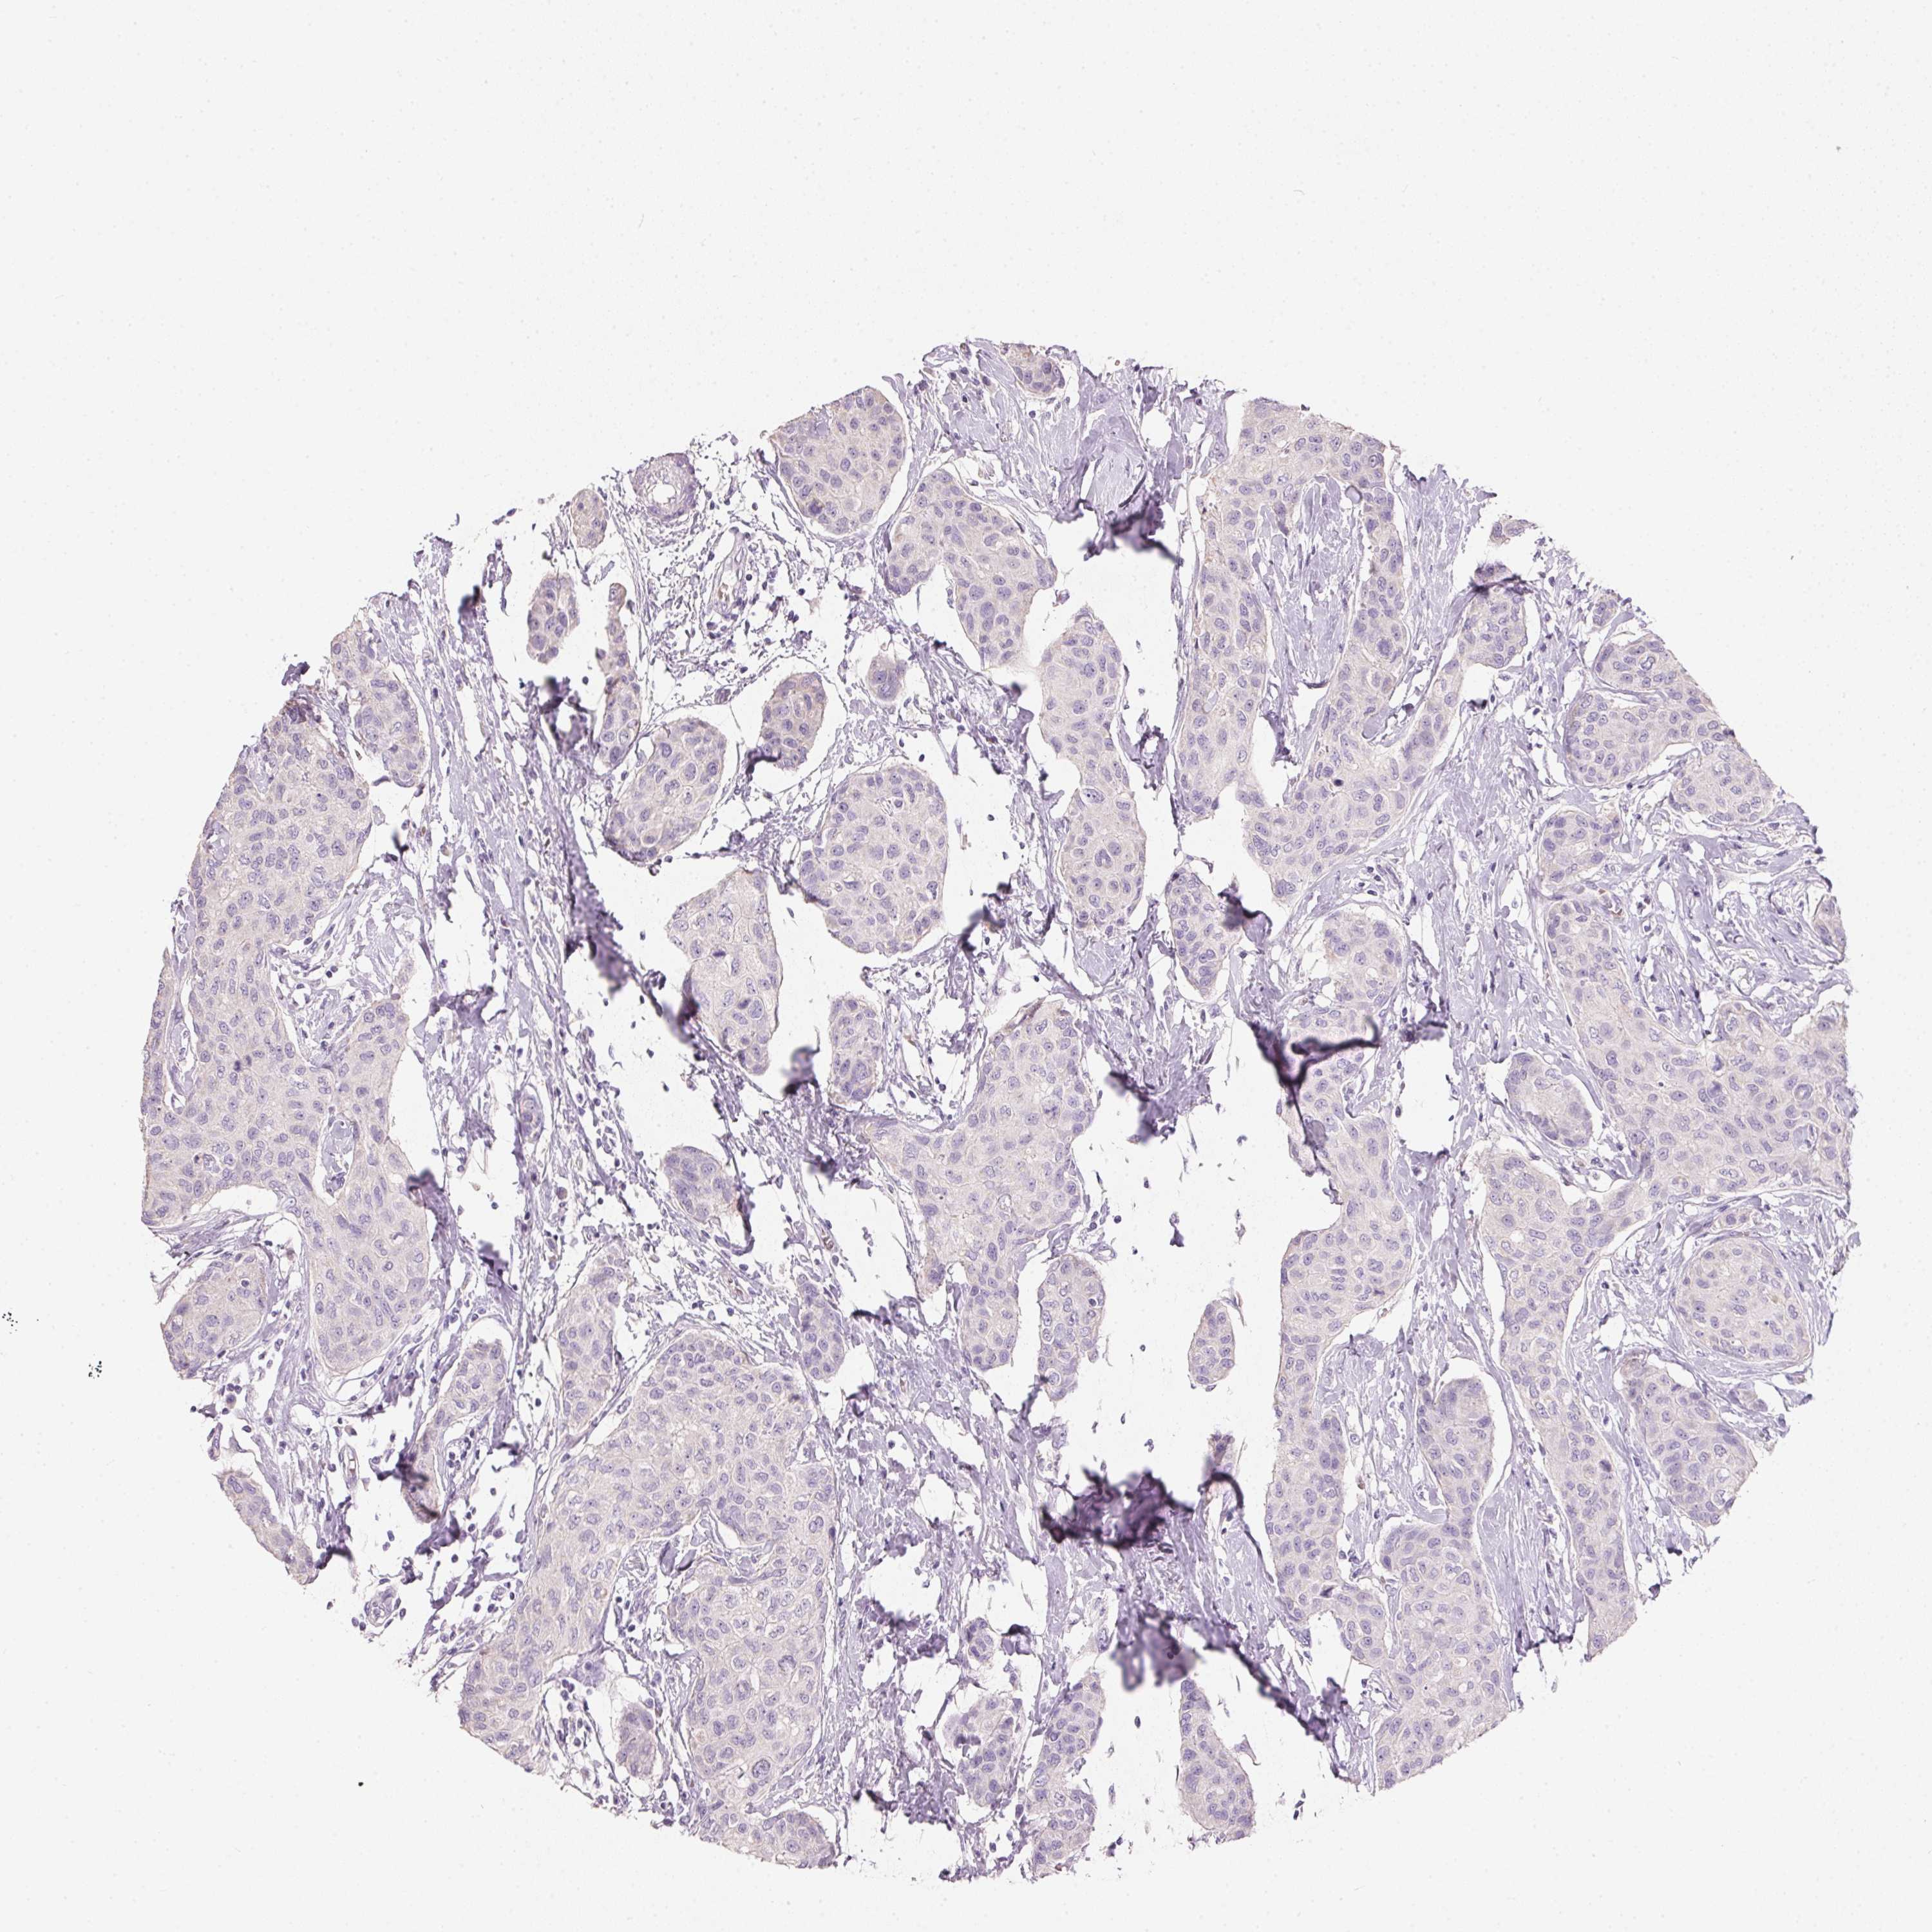

CANCER BREAST CANCER Show tissue menu

BRCA TCGA BRCA VALIDATION PROTEIN EXPRESSION

ANTIBODIES

AND

VALIDATION